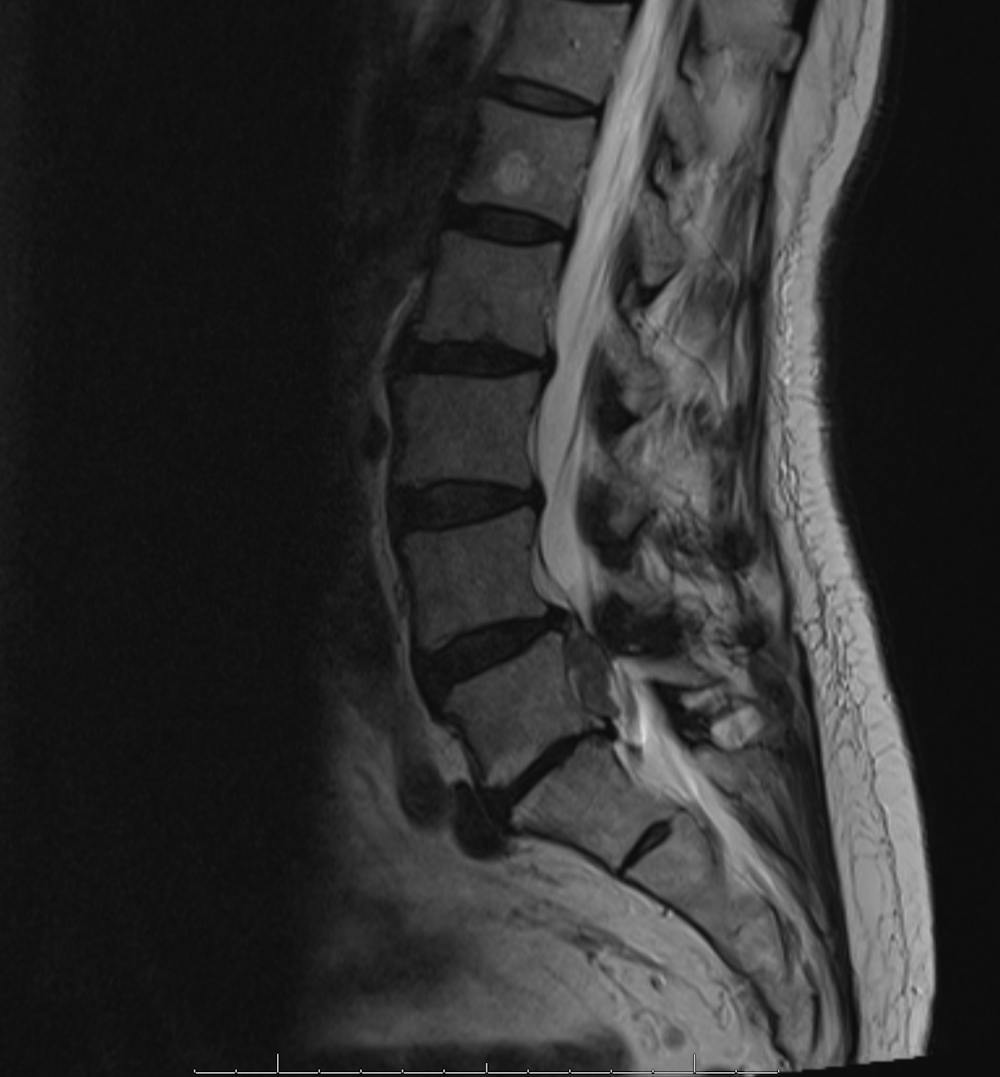

Ruptures or tears in the annulus fibrosus in a disc leads to moderate-to-severe lower back pain. This device was developed ease suffering, improve surgical outcomes, and prevent a recurrence of herniation, and avoid the need for an aggressive removal of the remaining disc nucleus.

The Barricaid anular closure device is implanted after a microdiscectomy (a procedure to resolve the pain and discomfort associated with a lumbar herniated disc). The device anchored to the adjacent vertebrae, in a minimally-invasive spine surgery, performed on an outpatient basis by Dr. Jonathan Stieber.

A disc herniation occurs when the inner walls of a disc in your spine pushes through the outer walls of the disc, causing pain. This leaves a hole that increases the risk of a patient suffering a return of the painful condition. You may be a good candidate for this groundbreaking treatment if:

Given that recurrent disc herniation occurs in ten to fifteen percent of patients who undergo primary lumbar disc surgery, Dr. Stieber may recommend that a Barricaid anular closing device be placed during your microdiscectomy procedure. He has seen firsthand how this groundbreaking surgical technique can help his patients avoid the risk of recurrent back injury and alleviate pain. For more information and to schedule a consultation, contact us.